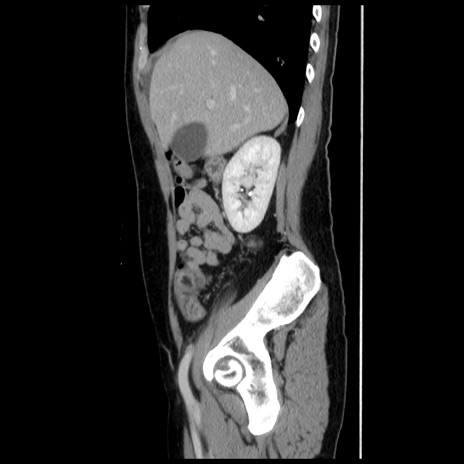

横断像

【症例】 50歳代女性

【主訴】 腹痛

【現病歴】前日生レバーを食べた。今朝に排便あり。 昼前に突然発症の腹痛を生じ、当院救急外来を受診した。

【既往歴】 子宮筋腫にてで子宮全摘後

【身体所見】 意識清明、腹部:平坦、軟、下腹部やや左を中心に圧痛・反跳痛あり、筋性防御あり

【データ】WBC 7800、CRP 0.07